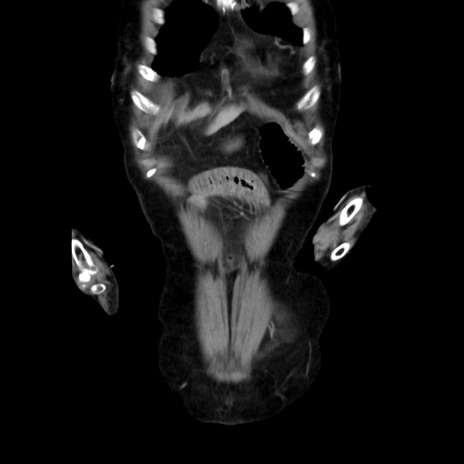

症例40(冠状断像)

【症例】90歳代女性

【主訴】腹痛・嘔吐

【現病歴】 食欲低下、嘔吐があり昨日他院受診。肺炎と診断され入院となる。入院後より腹部全体に圧痛あり。胃管留置され経過みていたが、症状持続するため、

当院転院となる。

【既往歴】胸椎圧迫骨折、胆石症

【身体所見】腹部:中央に激痛あり、圧痛あり、反跳痛不明

【データ】WBC 17100、CRP 18.82

他院CT

横断像